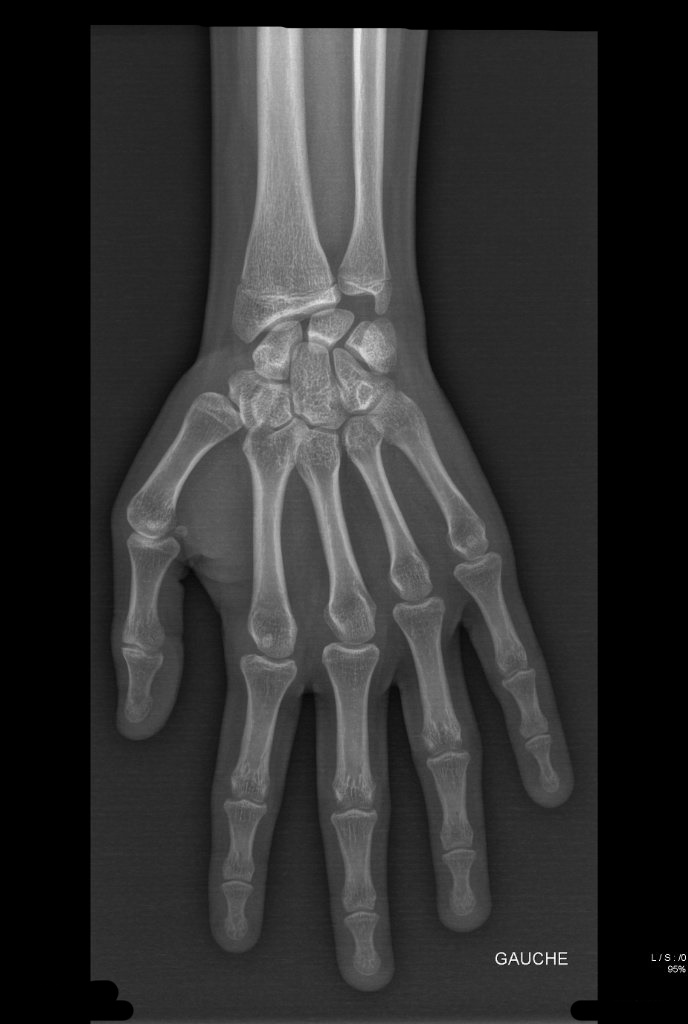

I had an appointement with my doc to get my xray prescription this morning and an appointement for the xray 30 mins ago and I officially have my wrist xray

Can you guys tell me the state of my plates pretty please ?

Pretty sure it's over but hey, gotta get a few opinions before (5'6 late 16m btw)